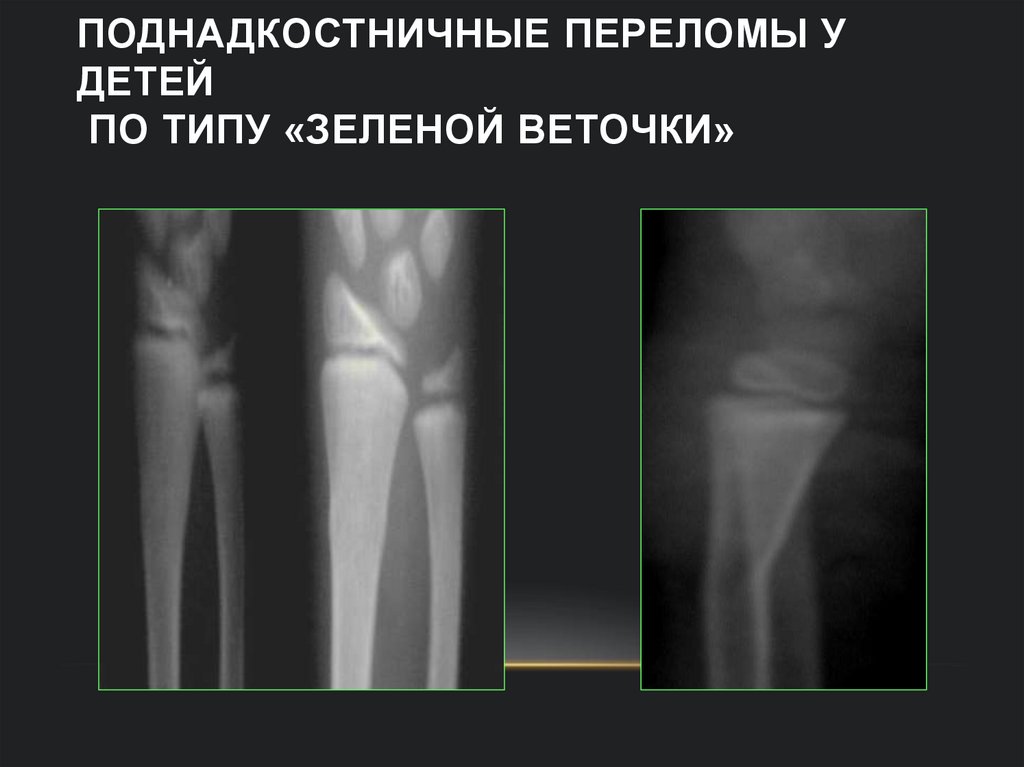

74. Поднадкостничные переломы у детей по типу «зеленой веточки»

ПОДНАДКОСТНИЧНЫЕ ПЕРЕЛОМЫ У

ДЕТЕЙ

ПО ТИПУ «ЗЕЛЕНОЙ ВЕТОЧКИ»

Схема рентгенологических симптомов

поднадкостничных переломов

скобка

ступенька